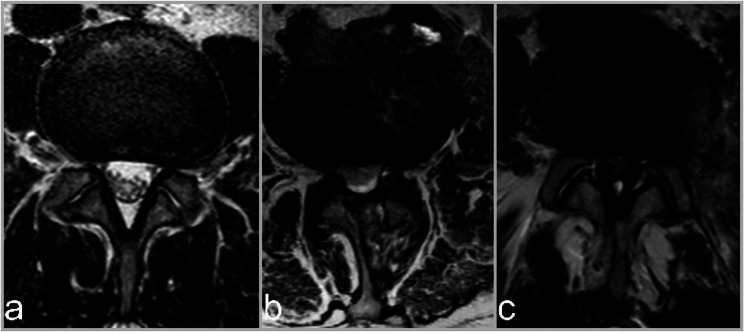

Background: Currently, the most widely used method to determine lumbar intervertebral disc degeneration is MRI. However, the evaluation of imaging signs of disc degeneration involves several subjective assessments. The aim of this study was to investigate differences in radiological assessments between two independent reports of the same MRI, emphasizing that the identical images were assessed twice by different raters.

Materials: MRI of the lumbar and cervical spine of a population-based random sample of women and a sample of female nurses, geriatric nurses and care workers as a subgroup with a relatively high level of work-related stress on the lumbar spine was performed. Each MRI was then assessed by two radiologists from the corresponding clinic that had examined the participant. Ten criteria were assessed: three continuous and seven categorical parameters. Agreement was assessed with bias and dispersion figures or agreement and Cohen's kappa for categorical parameters.

Conclusion: The interrater reliability of MRI readings of the lumbar spine is greater when clearly defined parameters and measurement methods are used. Therefore, it should be investigated which easy to use rating scales can be implemented in daily clinical practice to make reports more reliable and useful for clinicians. One way to reduce subjectivity might be the use of reference images.